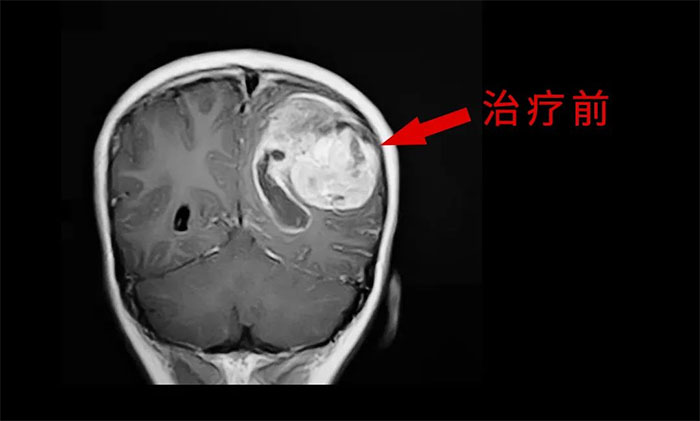

目前,腦膠質(zhì)瘤的治療方面,倡導(dǎo)MDT多學(xué)科診治,神經(jīng)外科、影像科、放射治療科、腫瘤科、病理科和康復(fù)科等多學(xué)科合作,遵循循證醫(yī)學(xué)原則,優(yōu)化和規(guī)范治療方案,采取個(gè)體化綜合治療,以期達(dá)到最大治療效益,盡可能延長(zhǎng)患者的無(wú)進(jìn)展生存期(PFS) 和總生存期(OS),提高生存質(zhì)量。

外科手術(shù)往往是膠質(zhì)瘤治療的第一步。手術(shù)原則是在最大范圍安全切除(maximal safe resection)腫瘤的同時(shí),保護(hù)神經(jīng)功能區(qū)。以解除占位征象和緩解顱內(nèi)高壓癥狀;解除或緩解因腦膠質(zhì)瘤引發(fā)的相關(guān)癥狀;獲得病理組織和分子病理,明確診斷;降低腫瘤負(fù)荷,為后續(xù)綜合治療提供條件。

放、化療等亦是不可或缺的重要治療手段,高級(jí)別膠質(zhì)瘤術(shù)后選擇標(biāo)準(zhǔn)同步放、化療可以取得顯著的生存獲益。

于耀宇主任特別指出,隨著腦血管介入技術(shù)快速發(fā)展,腦膠質(zhì)瘤術(shù)后超選介入化療聯(lián)合同步放療的效用正逐漸為大家所認(rèn)識(shí)。超選介入化療,是利用微導(dǎo)管技術(shù)直接將藥物通過(guò)供血?jiǎng)用},灌注到顱內(nèi)腫瘤組織區(qū)域,避免了傳統(tǒng)口服或靜脈注射藥物,要經(jīng)過(guò)全身代謝后才能到達(dá)腫瘤區(qū)域?蓽p輕全身毒性反應(yīng),延長(zhǎng)化療藥在腫瘤內(nèi)的滯留時(shí)間,更好地殺傷腫瘤細(xì)胞。

最后,于耀宇主任表示,膠質(zhì)瘤固然兇險(xiǎn),但我們應(yīng)當(dāng)正確認(rèn)識(shí)疾病,不盲目悲觀,更不應(yīng)輕易放棄治療。隨著醫(yī)療技術(shù)水平和治療手段的不斷提高,膠質(zhì)瘤患者在接受規(guī)范的治療后,延長(zhǎng)生存期已成為可能,大可不必“談瘤色變”。